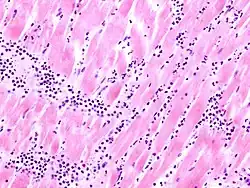

Acute myocardial infarction

Mikro: Koagulationsnekrose, Einblutungen. Die Myozyten zeigen eine verstärkte Eosinophilie und Kontraktionsbanden quer durch die Herzmuskelfasern. Typische Zellparameter wie Querstreifung, Zellkerne und Zellgrenzen gehen verloren. Das Infarktareal wird von einer Hyperämischen/hämorrhagischen Randzone begrenzt. Im Verlauf zunehmende leukozytäre Demarkation und Phagozytose des nekrotischen Gewebes, sowie Einwanderung von Fibroblasten mit Ausbildung eines narbigen Ersatzgewebes.

Makro: Lehmfarbene Abblassung mit hyperämischem/hämorrhagischem Randsaum.

Kompl.: Herzwandruptur mit Perikardtamponade (i.d.R. zwischen dem 3. und 10. Tag), Herzwandaneurysma, Papillarmuskelnekrose mit Sehnenfadenabriß, Herzrhythmusstörungen, Re-Infarkt, Herzinsuffizienz.